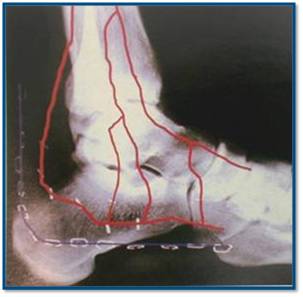

Разница между информацией полученной Р-графески и КТ - огромная.

Пример.

PDF, 134 Kb

Б-ной прооперирован по АО, применялась аутопластика из крыла подвздошной кости. На фото больной через 1 мес. Через 4 мес. - физический труд, осмотр через год - жалоб и претензий нет. До нас обращался в два лечебных учреждения, перелом не диагностирован. Был суд. Пациент процесс выиграл.

Больной гражданин РФ. Травма в Казахстане, здесь же и оперирован.

Виктор.

Во время операции была восстановлена суставная поверхность пяточной кости, после чего появилась надежда на восстановление нормальной функции подтаранного сустава. Кроме того, заполнена аутотрансплантатом критическая полость тела пяточной кости, которая хорошо вида на КТ.

В чем был смысл демонстрации? Диссонанс данных Р-граммы и данными КТ, операции.

Уверен, что без операции функционально результат был бы хуже (внутрисуставной перелом со смещением отломков), рентгенологически - без пластины пяточная кость смотрелась бы симпатичнее.